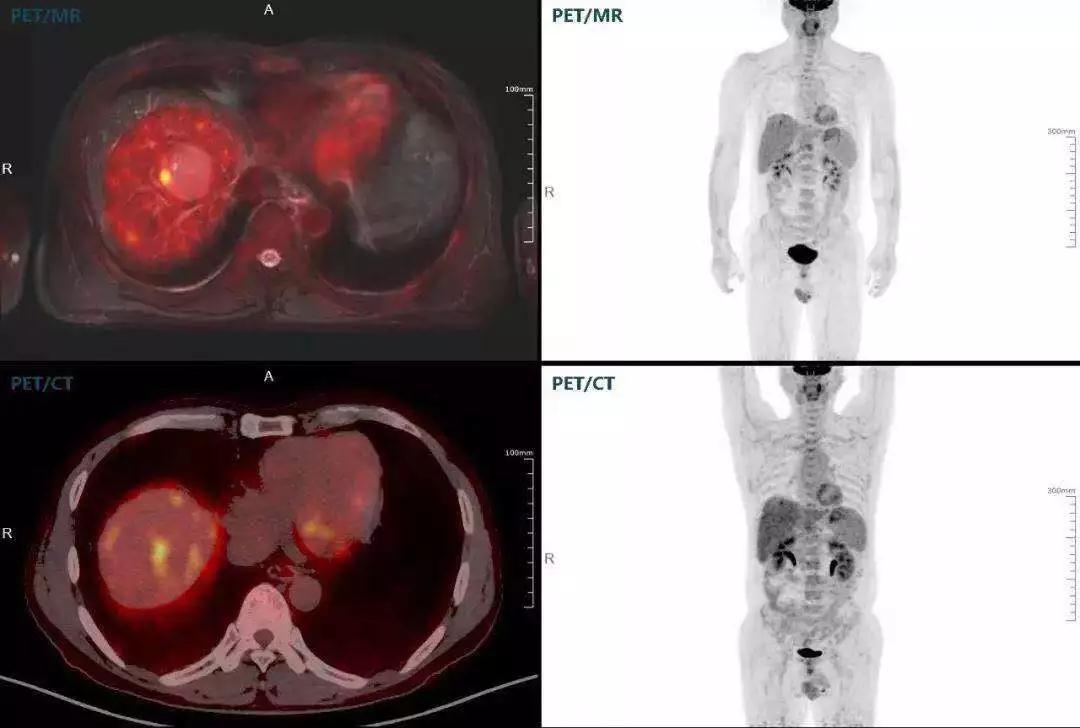

肝癌

聯(lián)影“時空一體”超清TOF PET/MR搭載的壓縮感知技術(shù),能夠同時實現(xiàn)16期成像,精準(zhǔn)捕獲肝臟動態(tài)影像的每一瞬間,同時兼顧早期與晚期等全部期相的完整病灶信息,實時、全方位鎖定病灶。同時,基于其2.8mm超高分辨率,能夠精細(xì)呈現(xiàn)腫瘤邊界信息,捕捉局部微小病灶與遠(yuǎn)端轉(zhuǎn)移灶,助力醫(yī)生精準(zhǔn)診斷。

(對于同一例肝臟惡性腫瘤,PET-CT與PET/MR成像對比??梢钥吹?,聯(lián)影PET/MR圖像對腫瘤邊界和FDG高濃聚區(qū)域清晰顯示。)